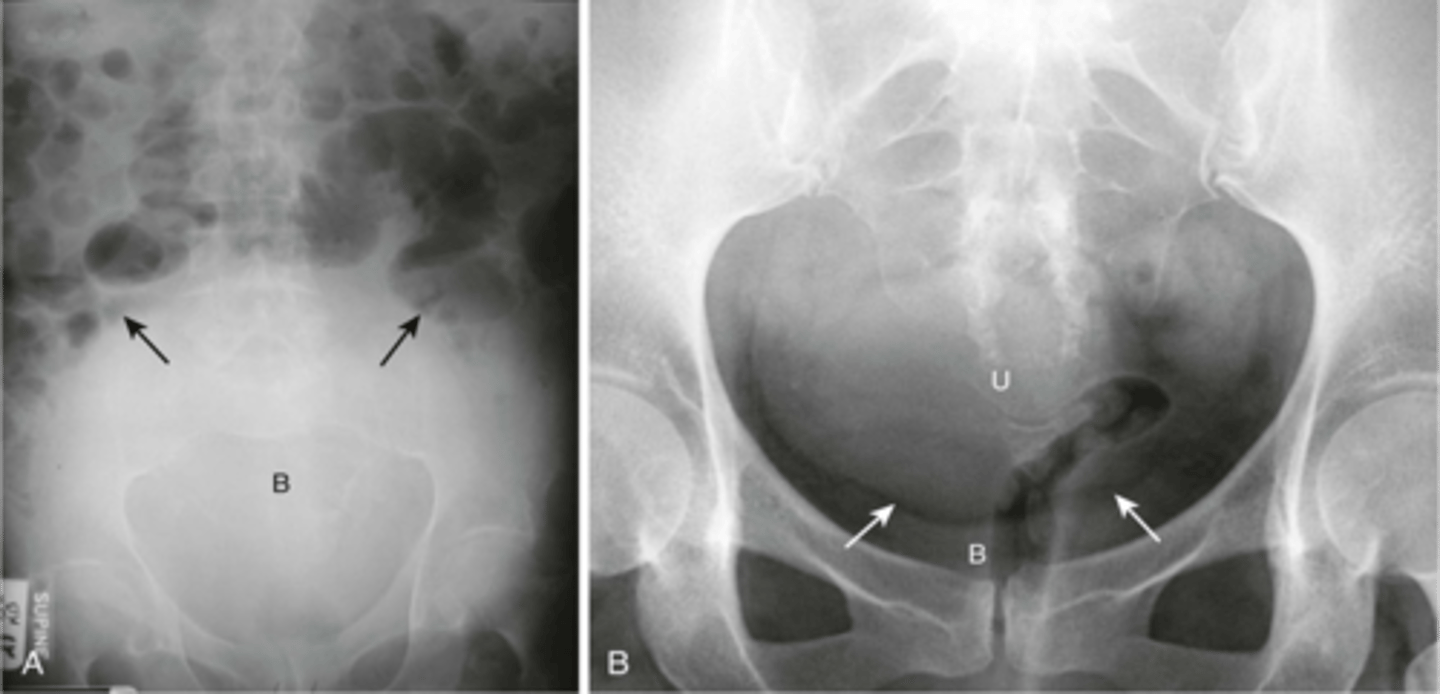

enlarged kidney

extremely enlarged organ or large masses, large cyst compressing and displacing other organs

enlarged bladder

usually appears at soft tissue mass, displacing bowel

renal imaging

xray (IV pyelography)- mainly replaced by US and CT

US- size, symmetry, lesions, kidney stones, obstructions, hydronephrosis

CT- characterize US abnormalities, study of choice for nephrolithiasis, trauma

MRI- renal cell cancer, mass

renal calculi

stone in R ureter, stone in L kidney

bladder imaging

X-ray- only enlargement

Ultrasound- asses wall thickness, tumors, stones, diverticula, estimate post-void volume

CT- characterize bladder cancer metastases and local disease

Cystoscopy- visualize bladder